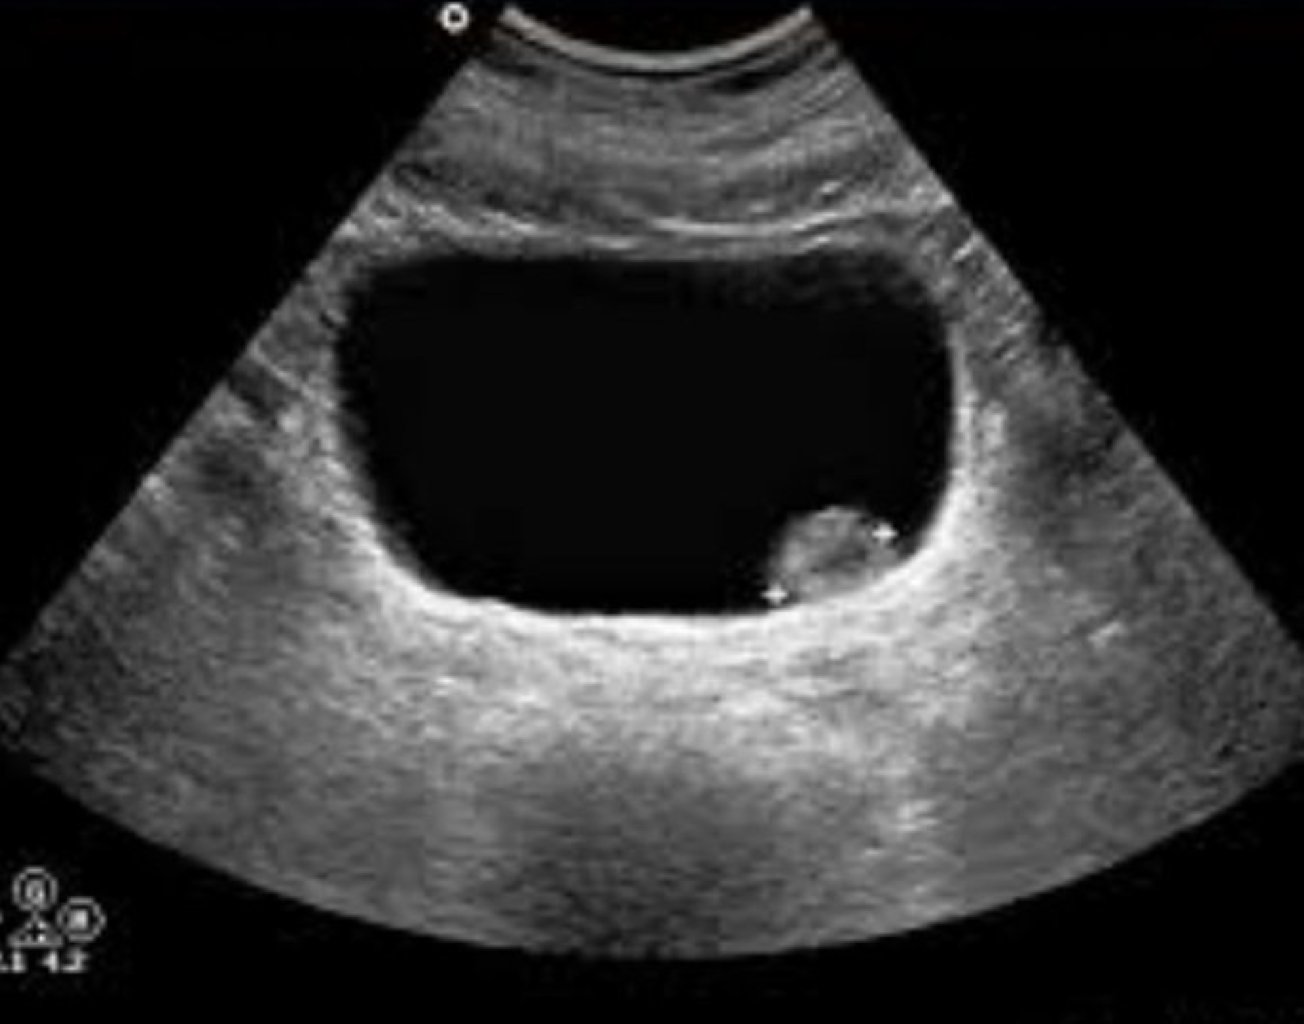

Kəskin xolesistit: Kəskin xolesistit ümumiyyətlə öd kisəsinin çıxışını bağlayan öd daşları və sonrak ...

Öd kisəsi xəstəliyinin səbəbləri: Öd daşının əmələ gəlməsinə səbəb olan müxtəlif amillər bunlardır: ...